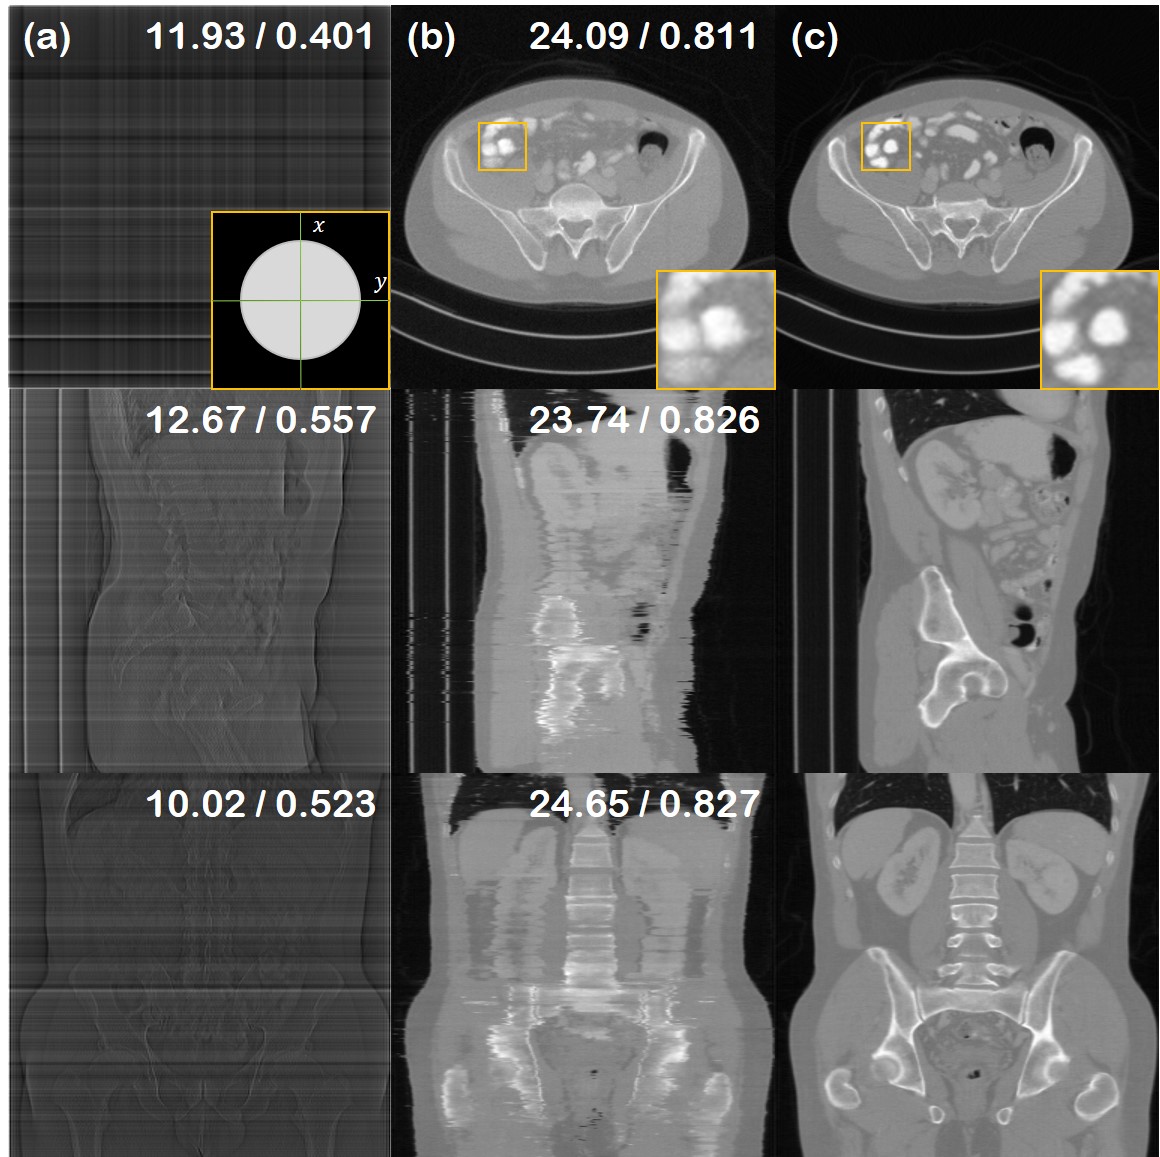

Figure 4: 90 LA-CT reconstruction results of the test data (First row: axial slice, second row: sagittal slice, third row: coronal slice). (a) FBP, (b) Zhang et al. [37], (c) Lahiri et al. [16], (d) Chung et al. [5], (e) proposed method, (f) ground truth. PSNR/SSIM values presented in the upper right corner. Green area in the inset of first row (a): measured, Yellow area in the inset of first row (a): not measured.

The results of the limited angle tomography is presented in Table 2 and Fig. 4. We test on the case where we have measurements in the [0,90]superscript090[0,90]^{\circ} regime, and no measurements in the [90,180]superscript90180[90,180]^{\circ} regime. Hence, the task is to infill the missing views. Consistent with what was observed from SV-CT experiments, we see that DiffusionMBIR improves over the conventional diffusion model-based method [5], and also outperforms other fully supervised methods, where we see even larger gaps in performance between the proposed method and all the other methods. Notably, Chung et al. [5] leverages no information from the adjacent slices, and hence has high degree of freedom on how to infill the missing angle. As the reconstruction is stochastic, we cannot impose consistency across the different slices. Often, this results in the structure of the torso being completely distorted, as can be seen in the first row of Fig. 4 (d). In contrast, our augmented prior imposes smoothness across frames, and also naturally robustly preserves the structure.